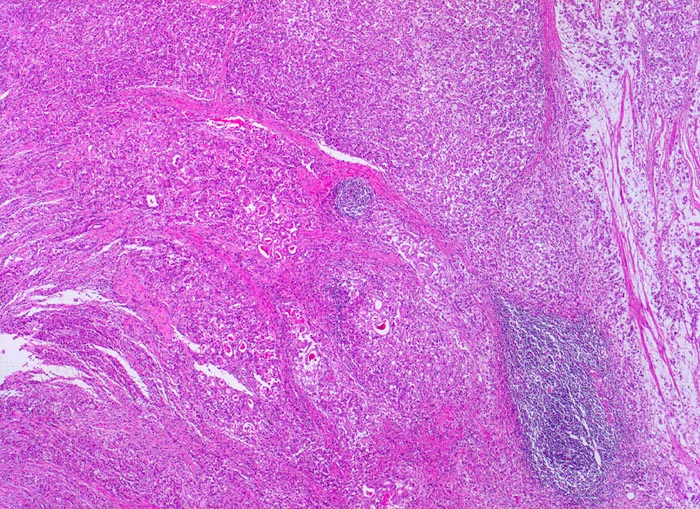

Adenokarzinom des Magens

Oesophagogastrischer Uebergang

Das Karzinom breitet sich diffus in der gesamten Magenwand aus. Rechts im Bild sieht man die durch den Tumor aufgesplitterte Muscularis propria.

Diffuse Verdickung und Versteifung der Magenwand im Sinne einer Linitis plastica bei intakter Schleimhautoberfläche. Aufhebung des Faltenreliefs.

Die Magenkarzinome können nach Lauren in einen intestinalen und einen diffusen Typ eingeteilt werden. Karzinome vom intestinalen Typ bestehen aus Karzinomdrüsen, welche einen umschriebenen expansiv wachsenden Tumor bilden. Der diffuse Typ besteht aus Tumorzellen, welche keine Drüsen bilden sondern die Magenwand einzeln oder in kleinen Verbänden diffus infiltrieren. Meist handelt es sich dabei um den histologischen Subtyp von Siegelringkarzinomen. Daneben gibt es auch eine Mischform mit Anteilen vom diffusen und vom intestinalen Typ.

Histologie

25